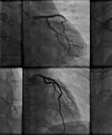

A Coronary Angiogram is a minimally invasive procedure to access the coronary circulation and blood filled chambers of the heart using a catheter. It is performed for both diagnostic and interventional purposes.

Coronary Angiogram procedure involves the placement of a catheter in an artery in the groin or arm area and threaded through the blood vessels to the heart. The doctor uses the angiogram to check for blocked or narrowed blood vessels in the heart.